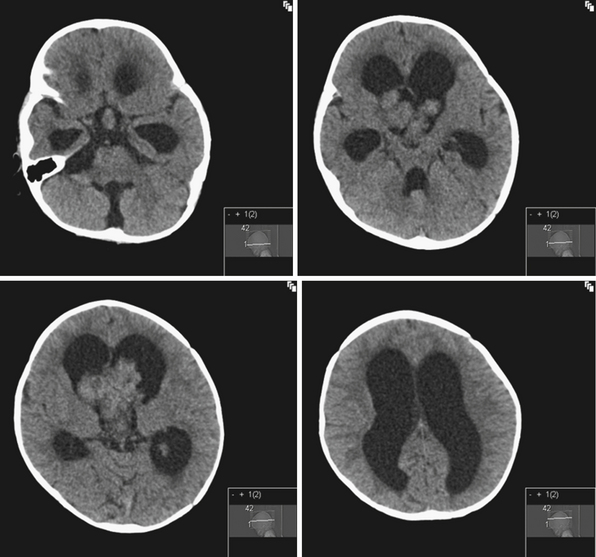

Hydrocephalus, CT scan – Stock Image – C018/0567 – Science Photo Library

Hydrocephalus | Radiology Case | Radiopaedia.org

Severe hydrocephalus | Radiology Case | Radiopaedia.org

Hydrocephalus | Radiology Case | Radiopaedia.org

Severe hydrocephalus | Radiology Case | Radiopaedia.org